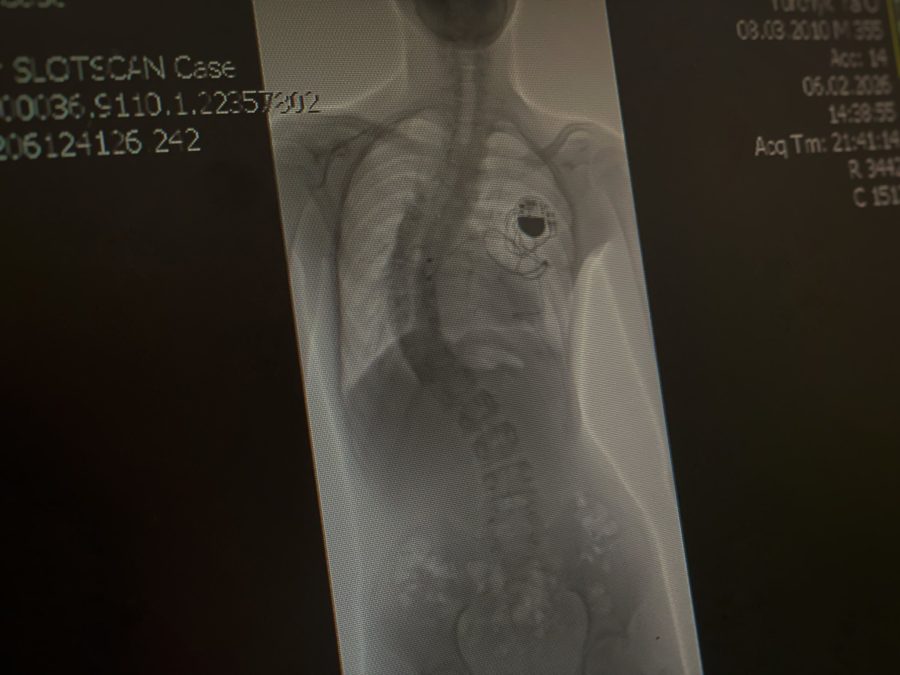

Хребет хлопця на рентгенному знімку. Фото: Дитяча Лікарня Святого Миколая

Один із провідних спінальних хірургів світу, американець Ізадор Ліберман, у Львові разом із лікарями дитячої лікарні Святого Миколая провів операцію 16-річному хлопцеві з кардіостимулятором і сколіозом найважчого, IV ступеня. Після операції викривлення хребта вдалося значно зменшити – з критичних 80° до 25°. Про це повідомили у пресслужбі медзакладу.